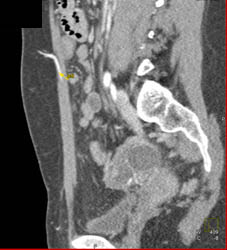

DIEP Flap Planning